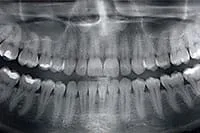

Panoramic X-rays

Our digital panoramic X-ray machine captures a highly detailed image of your entire mouth and clearly shows your teeth, sinuses, jaw joints and the bone levels surrounding your teeth. Digital X-rays make diagnosis and treatment planning far more precise and efficient.